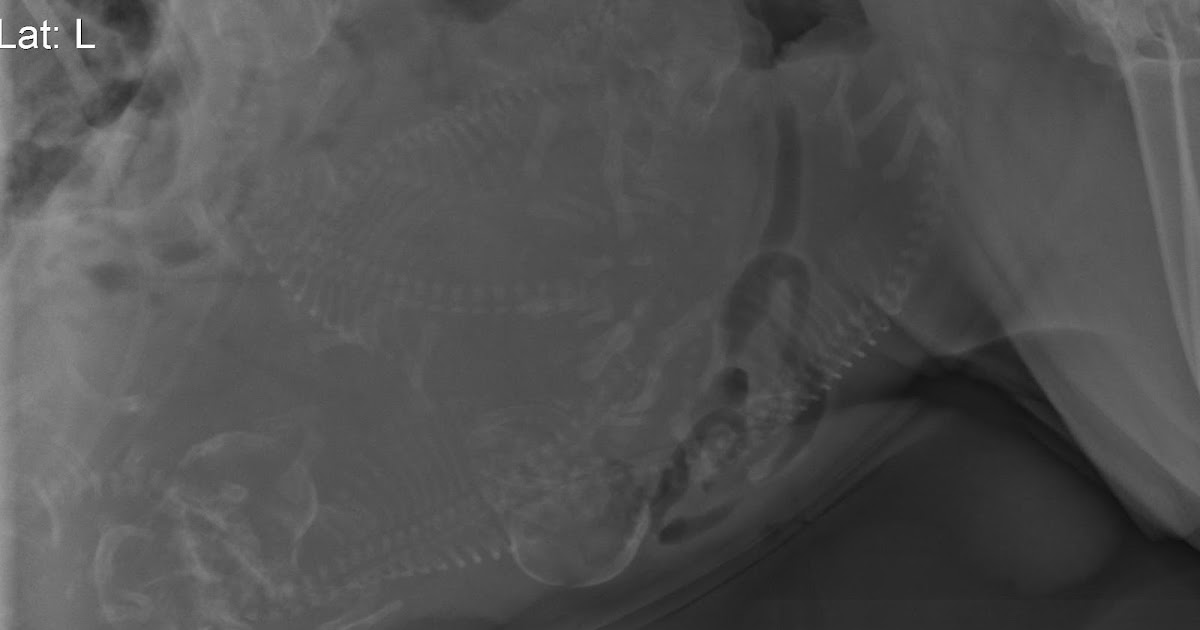

From docslib.org

Apgar Score After Induction of Anesthesia for Canine Cesarean Section Anesthesia For Canine Cesarean Section A caesarean section is the surgical removal of fetuses from the pregnant bitch. Anesthesia can be a scary thought for any patient, let alone when you are performing anesthesia on a patient that is pregnant! Anaesthesia of the caesarean section patient is complicated because the anaesthetist must consider the unique physiology of not only the dam but the foetus (es). Anesthesia For Canine Cesarean Section.